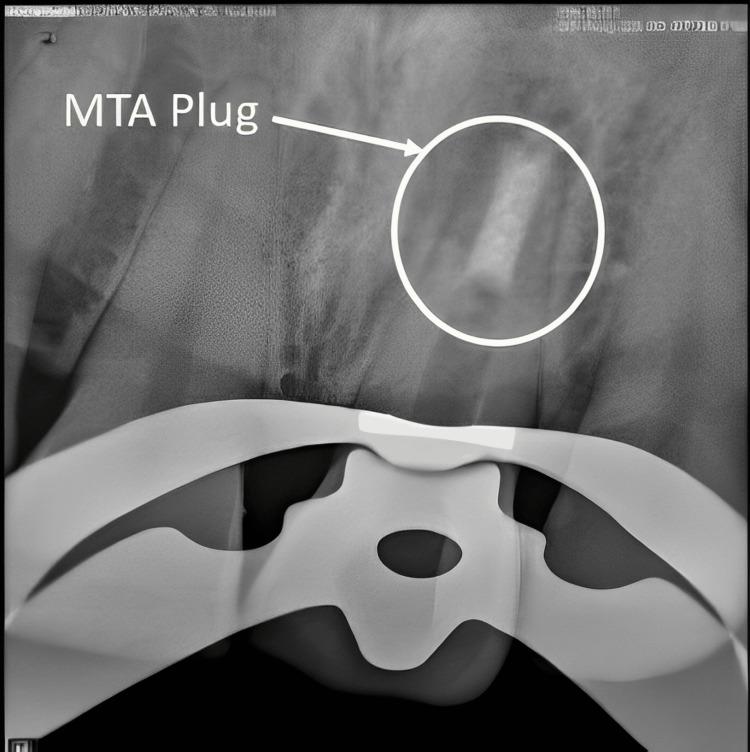

Apexification is a crucial procedure for achieving apical healing in non-vital teeth with open apices. Traditionally, calcium hydroxide has been used for this purpose, but it has significant drawbacks, including prolonged treatment duration, increased risk of root fracture, and the potential for porous barrier formation. Mineral trioxide aggregate (MTA) has emerged as a superior alternative due to its biocompatibility, faster setting time, and better sealing properties. However, MTA extrusion into periradicular tissues can cause persistent discomfort. The use of an internal matrix such as platelet-rich fibrin (PRF) can help contain MTA within the root canal, enhancing treatment outcomes. A 35-year-old female presented with dull, aching pain in tooth 21, a history of trauma 10 years prior, and incomplete root canal therapy 2 years ago. Diagnosis revealed an open apex with chronic apical periodontitis and pulpal necrosis. Initial management involved canal disinfection with sodium hypochlorite (NaOCl) and calcium hydroxide as intracanal medication. One week later, the patient returned asymptomatic. PRF was prepared from the patient's blood and used as an internal matrix. Mineral trioxide aggregate was then placed against the PRF membrane to form an apical stop. The canal was subsequently obturated with thermoplasticized gutta-percha and restored with composite resin. The use of PRF and MTA provided effective apical sealing, preventing material extrusion and promoting tissue healing. The PRF matrix facilitated the controlled placement of MTA, minimizing complications and enhancing periapical healing. The combination of PRF as an internal matrix and MTA for apical barrier formation represents a promising approach for managing non-vital teeth with open apices. This technique ensures better control over material placement, reduces treatment time, and improves the overall success of endodontic therapy. The aim of this case report is to describe the endodontic management of a non-vital permanent tooth with an open apex and chronic apical periodontitis using a single-step apical barrier technique with MTA and PRF as an internal matrix.

根尖诱导成形术是使根尖孔开放的无髓牙实现根尖愈合的关键步骤。传统上,氢氧化钙一直用于此目的,但它有显著缺点,包括治疗时间延长、根折风险增加以及形成多孔屏障的可能性。由于其生物相容性、更快的凝固时间和更好的封闭性能,矿物三氧化物凝聚体(MTA)已成为一种更优的替代材料。然而,MTA挤出到根尖周组织中会导致持续不适。使用富含血小板纤维蛋白(PRF)等内部基质有助于将MTA限制在根管内,提高治疗效果。一名35岁女性,主诉21号牙钝痛、隐痛,10年前有外伤史,2年前根管治疗未完成。诊断显示根尖孔开放伴慢性根尖周炎和牙髓坏死。初始治疗包括用次氯酸钠(NaOCl)和氢氧化钙进行根管消毒并作为根管内用药。一周后,患者复诊时无症状。从患者血液中制备PRF并用作内部基质。然后将矿物三氧化物凝聚体放置在PRF膜上以形成根尖屏障。随后用热塑牙胶充填根管并用复合树脂修复。PRF和MTA的使用提供了有效的根尖封闭,防止材料挤出并促进组织愈合。PRF基质有助于MTA的可控放置,将并发症降至最低并促进根尖周愈合。PRF作为内部基质与MTA联合用于根尖屏障形成是处理根尖孔开放的无髓牙的一种有前景的方法。该技术可更好地控制材料放置,缩短治疗时间并提高根管治疗的总体成功率。本病例报告的目的是描述使用以MTA和PRF作为内部基质的单步根尖屏障技术对一颗根尖孔开放且患有慢性根尖周炎的无髓恒牙进行根管治疗的情况。